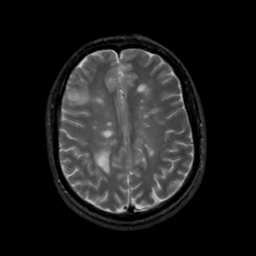

MR Study #6, March 17, 1991 -- Slice #34

[Home][Help][Clinical][Tour 1][Tour 2] Slice 34